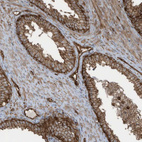

Immunohistochemical staining of human stomach shows strong membranous positivity in glandular cells.